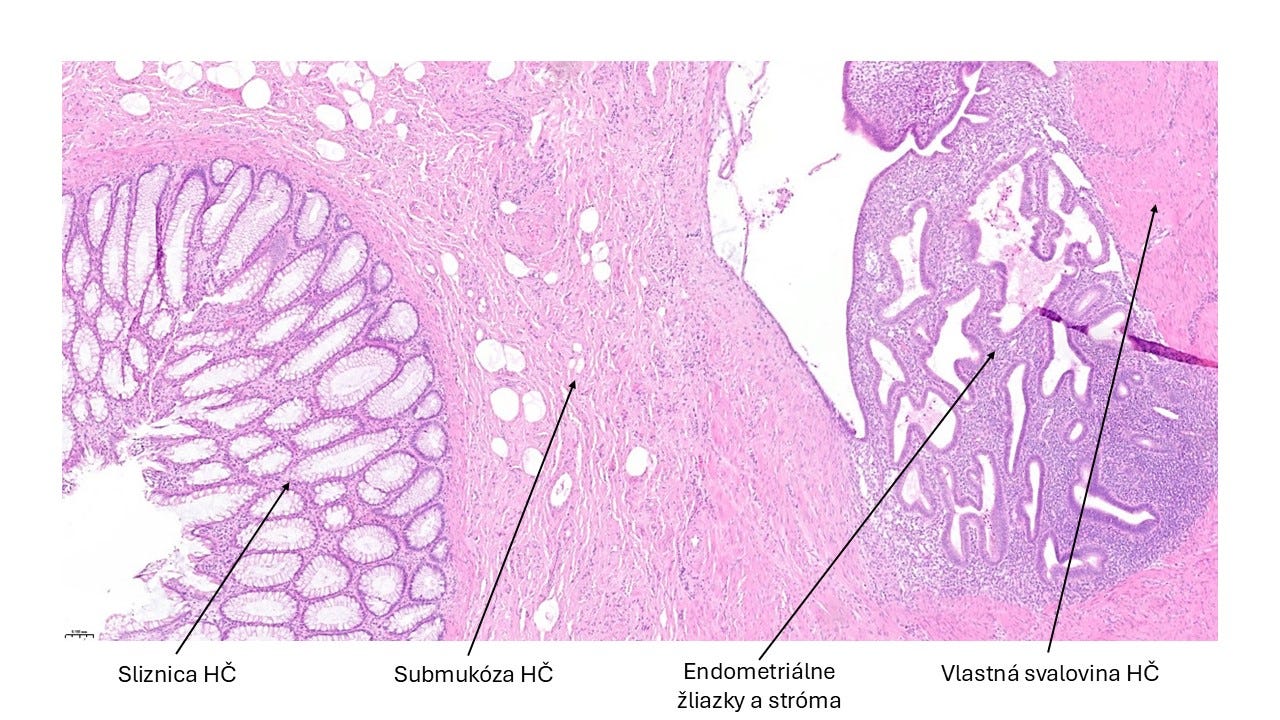

Kazuistika mesiaca

📝 Tento prípad mi „pristál” na stole počas tvorby tohto newslettera (úroveň 2/5). Karma predsa len existuje. 🙂

Resekát časti hrubého čreva 38-ročnej ženy, s mnohopočetnými suspektnými ložiskami v jej stene a pod viscerálnym peritoneom, ktoré boli viditeľné voľným okom.

✅ D. Endometrióza hrubého čreva.

💡 Endometrióza je prítomnosť „ostrovčekov” histologicky normálneho endometria v iných tkanivách a orgánoch než je výstelka (sliznica) dutiny maternice.

V ektopických lokalitách podliehajú endometriálne žliazky a stróma rovnako hormonálnym zmenám ako v dutine maternice.

V dôsledku toho vznikajú ložiská krvácania, ktoré sa postupne organizujú, neskôr peritoneálne zrasty v prípade GIT-u, atď. Klinický obraz je preto rôznorodý, v závislosti od lokality postihnutého tkaniva.